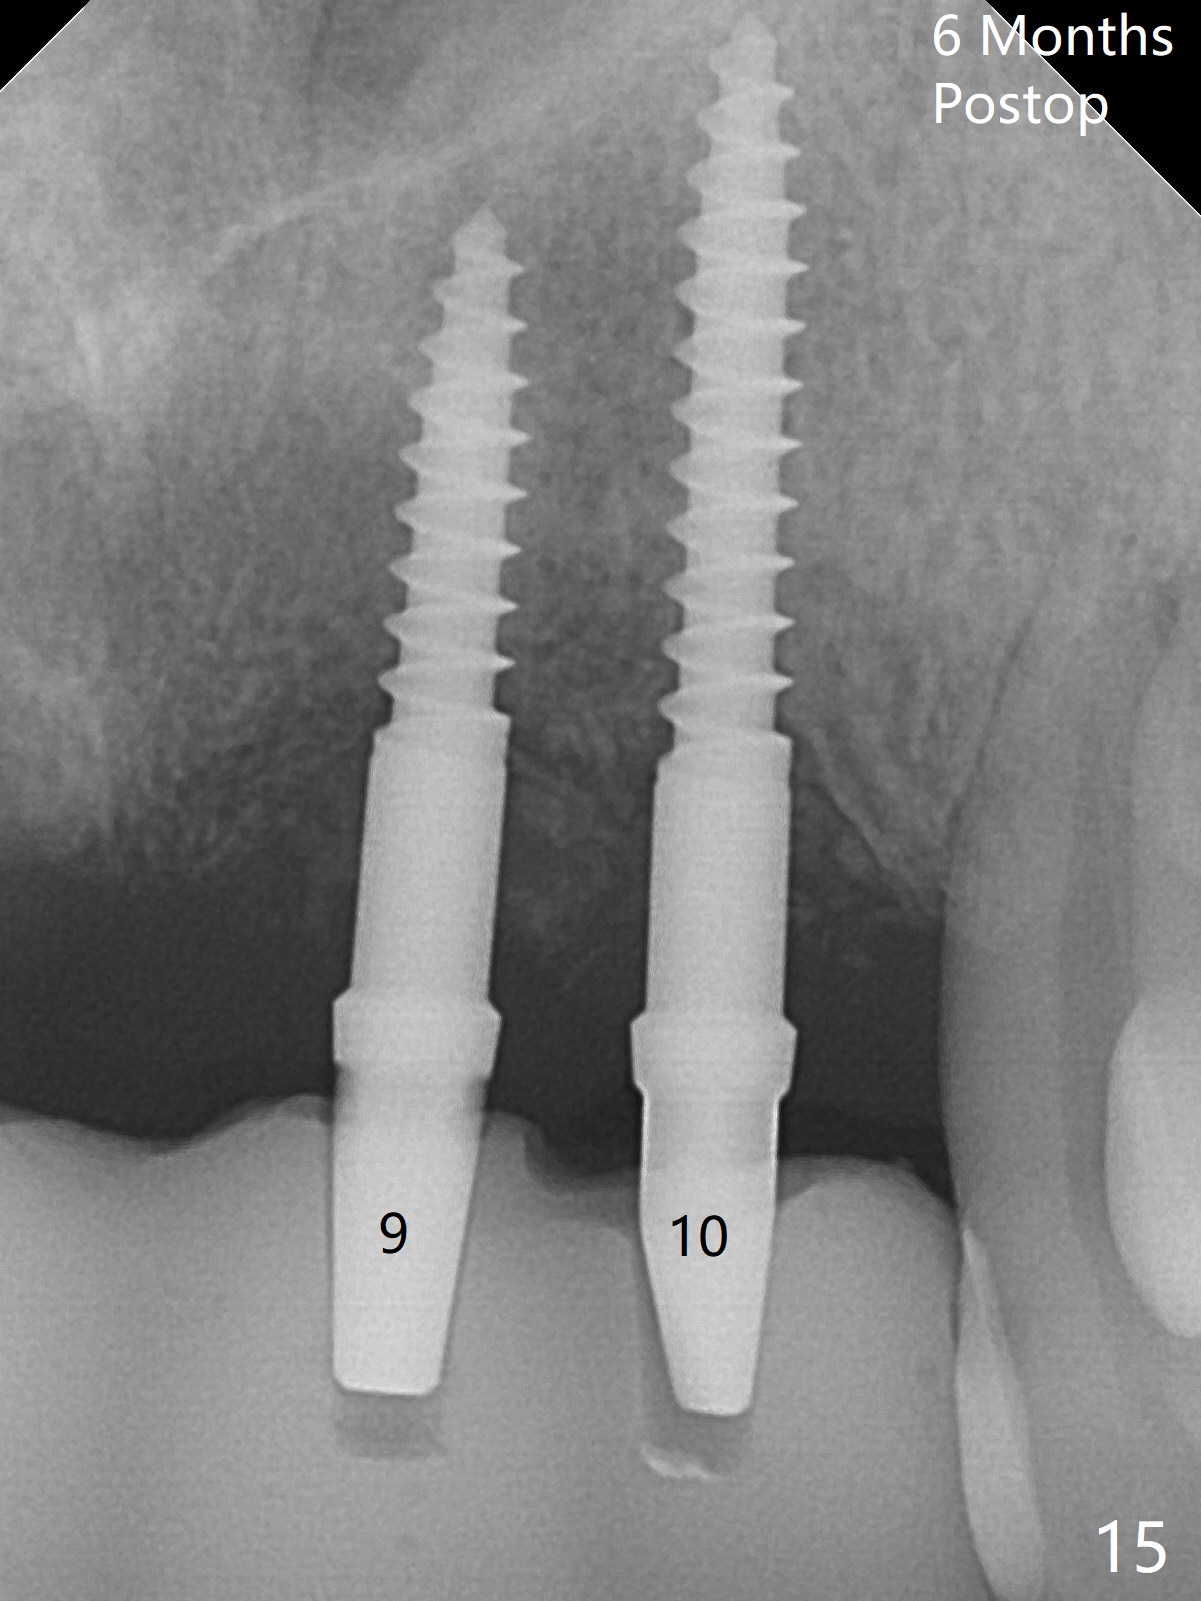

Although the ridge of the maxillary anterior ridge looks moderate in width (Fig.1), the bone is ~4 mm buccopalatally. Suction down surgical stent (Fig.2') made from the lab-fabricated provisional (Fig.2) will be used to check the position and trajectory of osteotomies. PAs taken after initial osteotomies (1.2 mm drill) show those at the central incisors tend to be mesial (close to the Incisive Canal *), while those at the lateral incisor sites distal (Fig.3,4). After adjustment, the position and trajectory of the osteotomies are acceptable (Fig.5,6). To reduce the chance of perforating the Incisive Canal (Fig.3,4 *), 2.5 mm 1-piece implants are inserted with >40 Ncm (Fig.7,8). After deep placement of the implants, Vanilla graft is placed at the crest (Fig.9,10 *). An immediate splinted provisional is fabricated from the suction down stent. The gingiva is healthy around the provisional (Fig.11) and the implants (Fig.12,13) 1 month postop. The provisional is adjusted monthly so that the interdental papillae can be elongated. No bone resorption is observed 6 months postop (Fig.14,15). Crowns are cemented 8 months postop (Fig.16-18). The keratinized gingiva appears to have formed the abutments 8 months postop immediately pre-cementation (Fig.19).